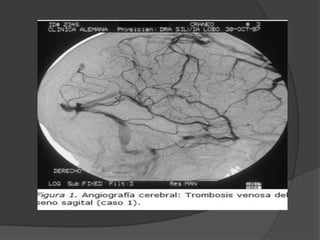

Trombosis venos cerebral

 Representa el 0,5 % de los ictus

 La TAC y la RNM constituyen las

principales pruebas de confirmación

diagnóstica.